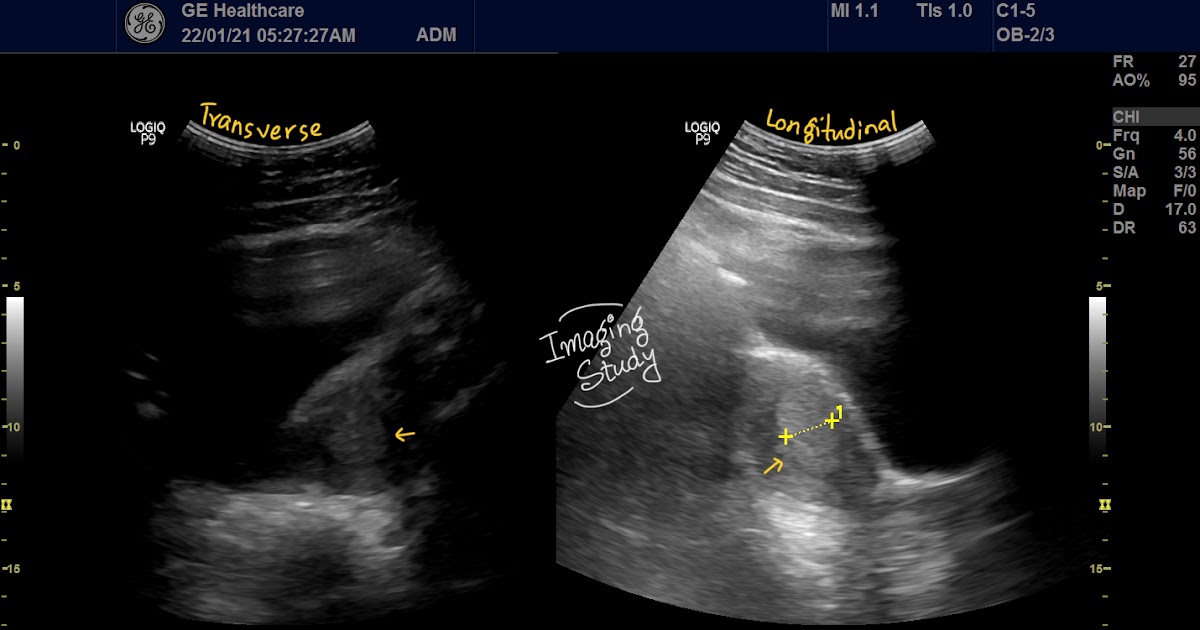

From www.imagingstudy.com

Case 26 Thickened Endometrium Imaging Study Thickened Endometrium Measurement The appearance, as well as. An endometrial thickness of less than 14 mm is typically considered normal at any stage of the menstrual cycle. Endometrial thickness is a commonly measured parameter on routine gynecological ultrasound and mri. The stripe can be anywhere from slightly less than 1 millimeter (mm) to slightly more than 16 mm in size. An endometrium normal. Thickened Endometrium Measurement.